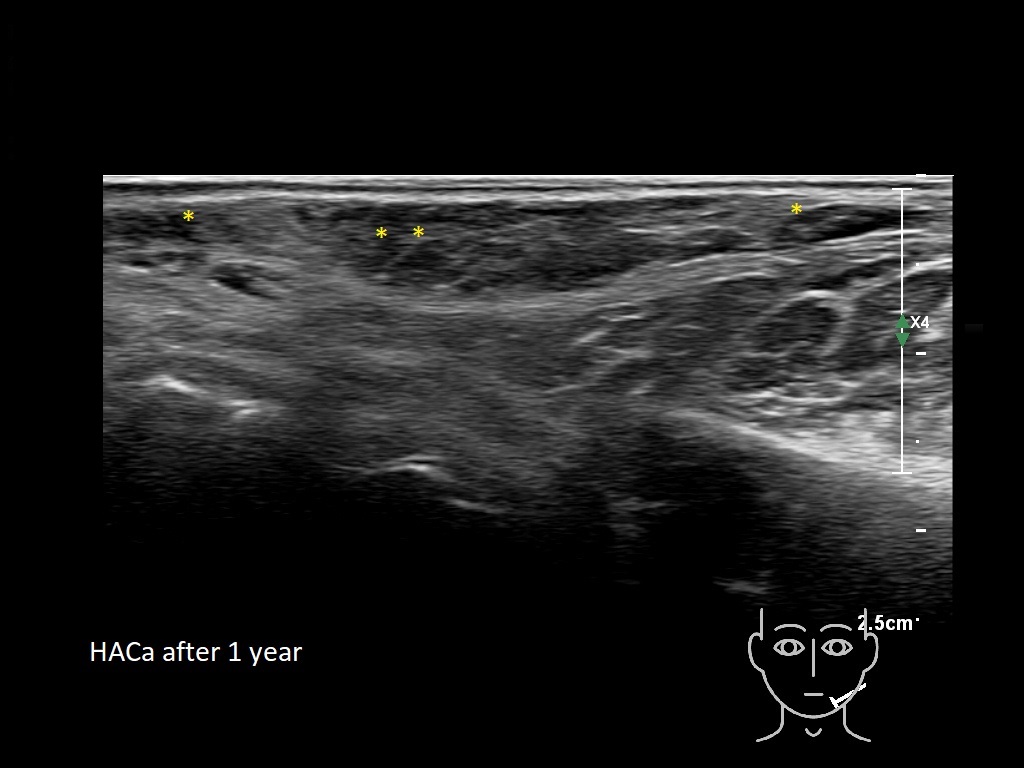

Draw in the second image below where the fillers are located. To check if your answer is correct, swipe the first image to the right.

Filler library

HAca 2a

HAca 3a

HAca 3a

HAca 4a